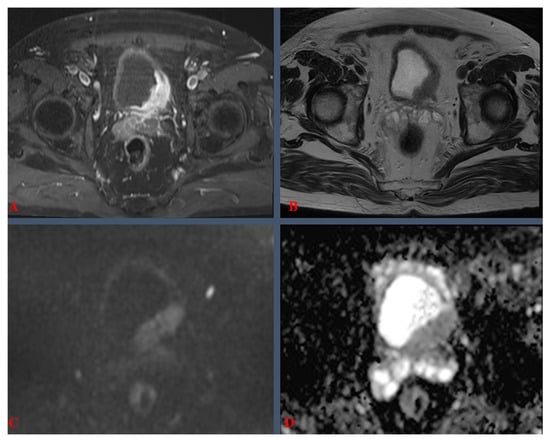

3.1. Definitions, Procedural Details, and Clinical Considerations

3.3. Imaging Parameters, Protocols, and Technical Specifications